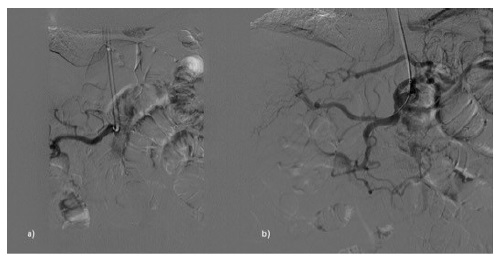

He was readmitted to the hospital 32 days after the discharge with abdominal pain, vomits, and constipation. Physical examination revealed abdominal pain and tenderness to palpation. CT scan showed ileum adhesion to a thickened cecum; the celiac trunk had a severe degree of stenosis, and the SMA was occluded. Analytically presented leukocytosis and an elevated c-reactive protein. He initiated antibiotic therapy (piperacillin + tazobactam) and parenteral nutrition. Seven days later, he was submitted to a celiac trunk primary stenting with a balloon-expandable stent (figures 3 and 4). Five days after the vascular procedure he was submitted to a right colectomy with segmental enterectomy by colorectal surgeons (figure 5). The postoperative period was uneventful, and he was discharged on the ninth day after the surgical procedure. At a 6-month follow-up, the patient remains without any gastrointestinal symptoms.